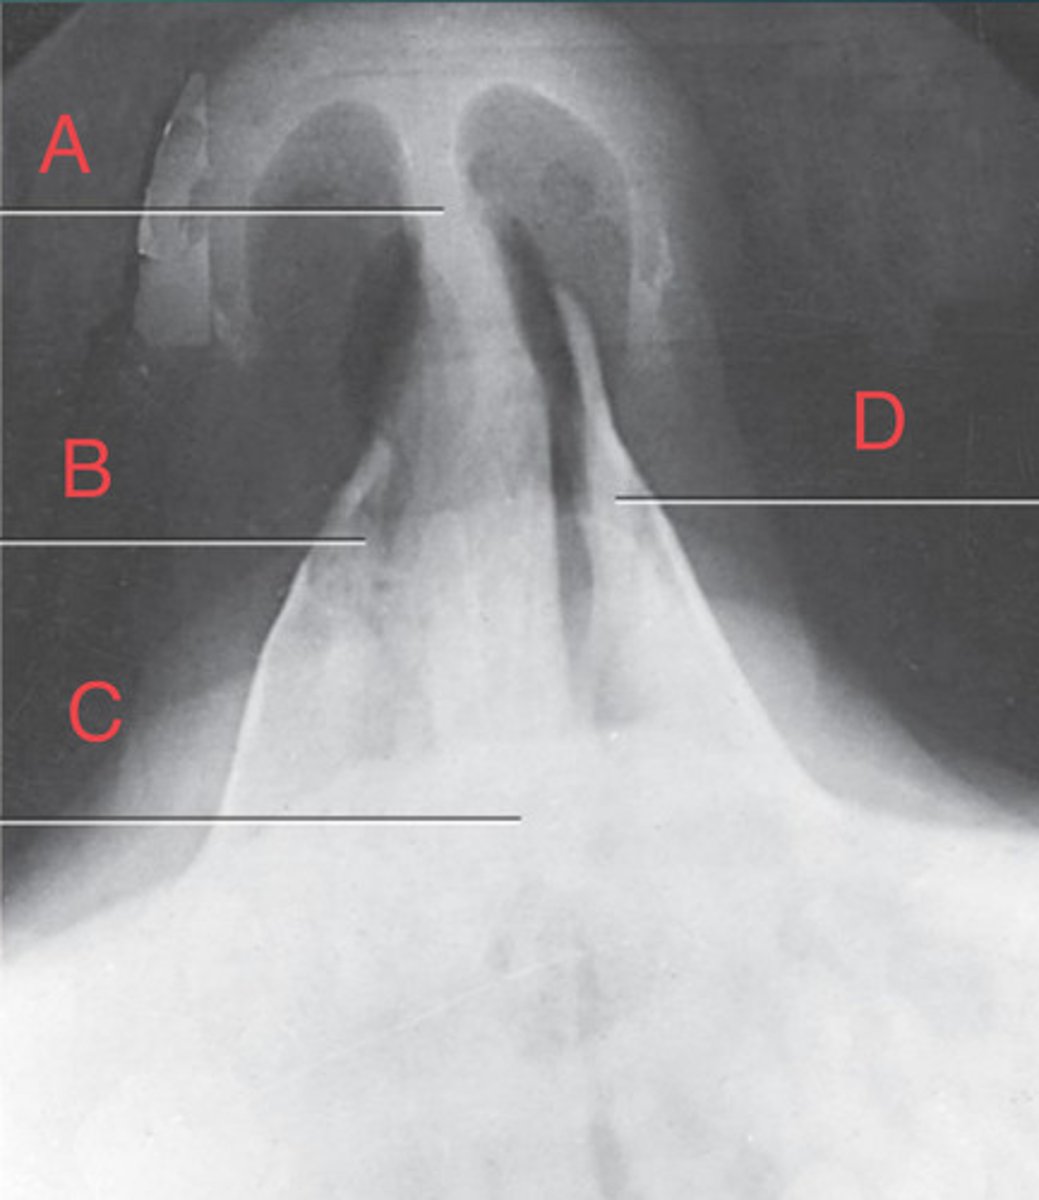

SMV sinuses

What position?

Sphenoid sinus of sphenoid bone

A.

R mandibular condyle of mandible

B.

R Mastoid air cells of temporal bone

C.

Nasal fossa

D.

L. Ethmoid sinus of ethmoid bone

E.

L maxillary sinus of maxilla

F.

L foramen ovale of sphenoid bone

G.

foramen spinosum of sphenoid bone

H.